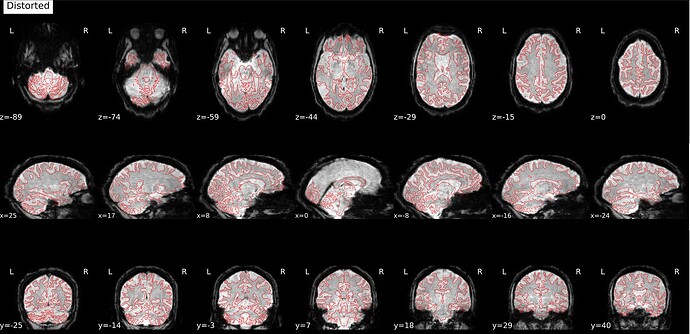

Hi everyone! I’m currently trying to use fMRIPrep to preprocess a dataset from openneuro (ds006072). fMRIPrep is running smoothly in general, but there seems to be a problem with SDC, which leads to a distorted and elongated corrected image. This is one example, but the data for all my sessions is similarly distorted:

This is what the distorted version looks like, before SDC: